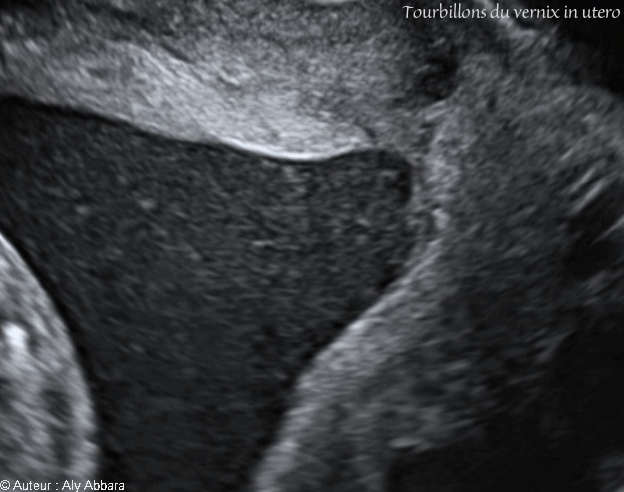

Fraquements de vernix tourbillonnant dans le liquide amniotique - الطلاء الدهني الجنيني العالق والمتحرك في السائل الأمنيوسي

• Image échographique animée montrant des tourbillons du vernix dans le liquide amniotique provoquées par les mouvements foetaux.

الطلاء الدهني الجنيني العالق والمتحرك في السائل الأمنيوسي إثر تحرك الجنين داخل الرحم

Des fragments de cet enduit se retrouvent en suspension dans le liquide amniotique sous forme de grumeaux blanchâtres.